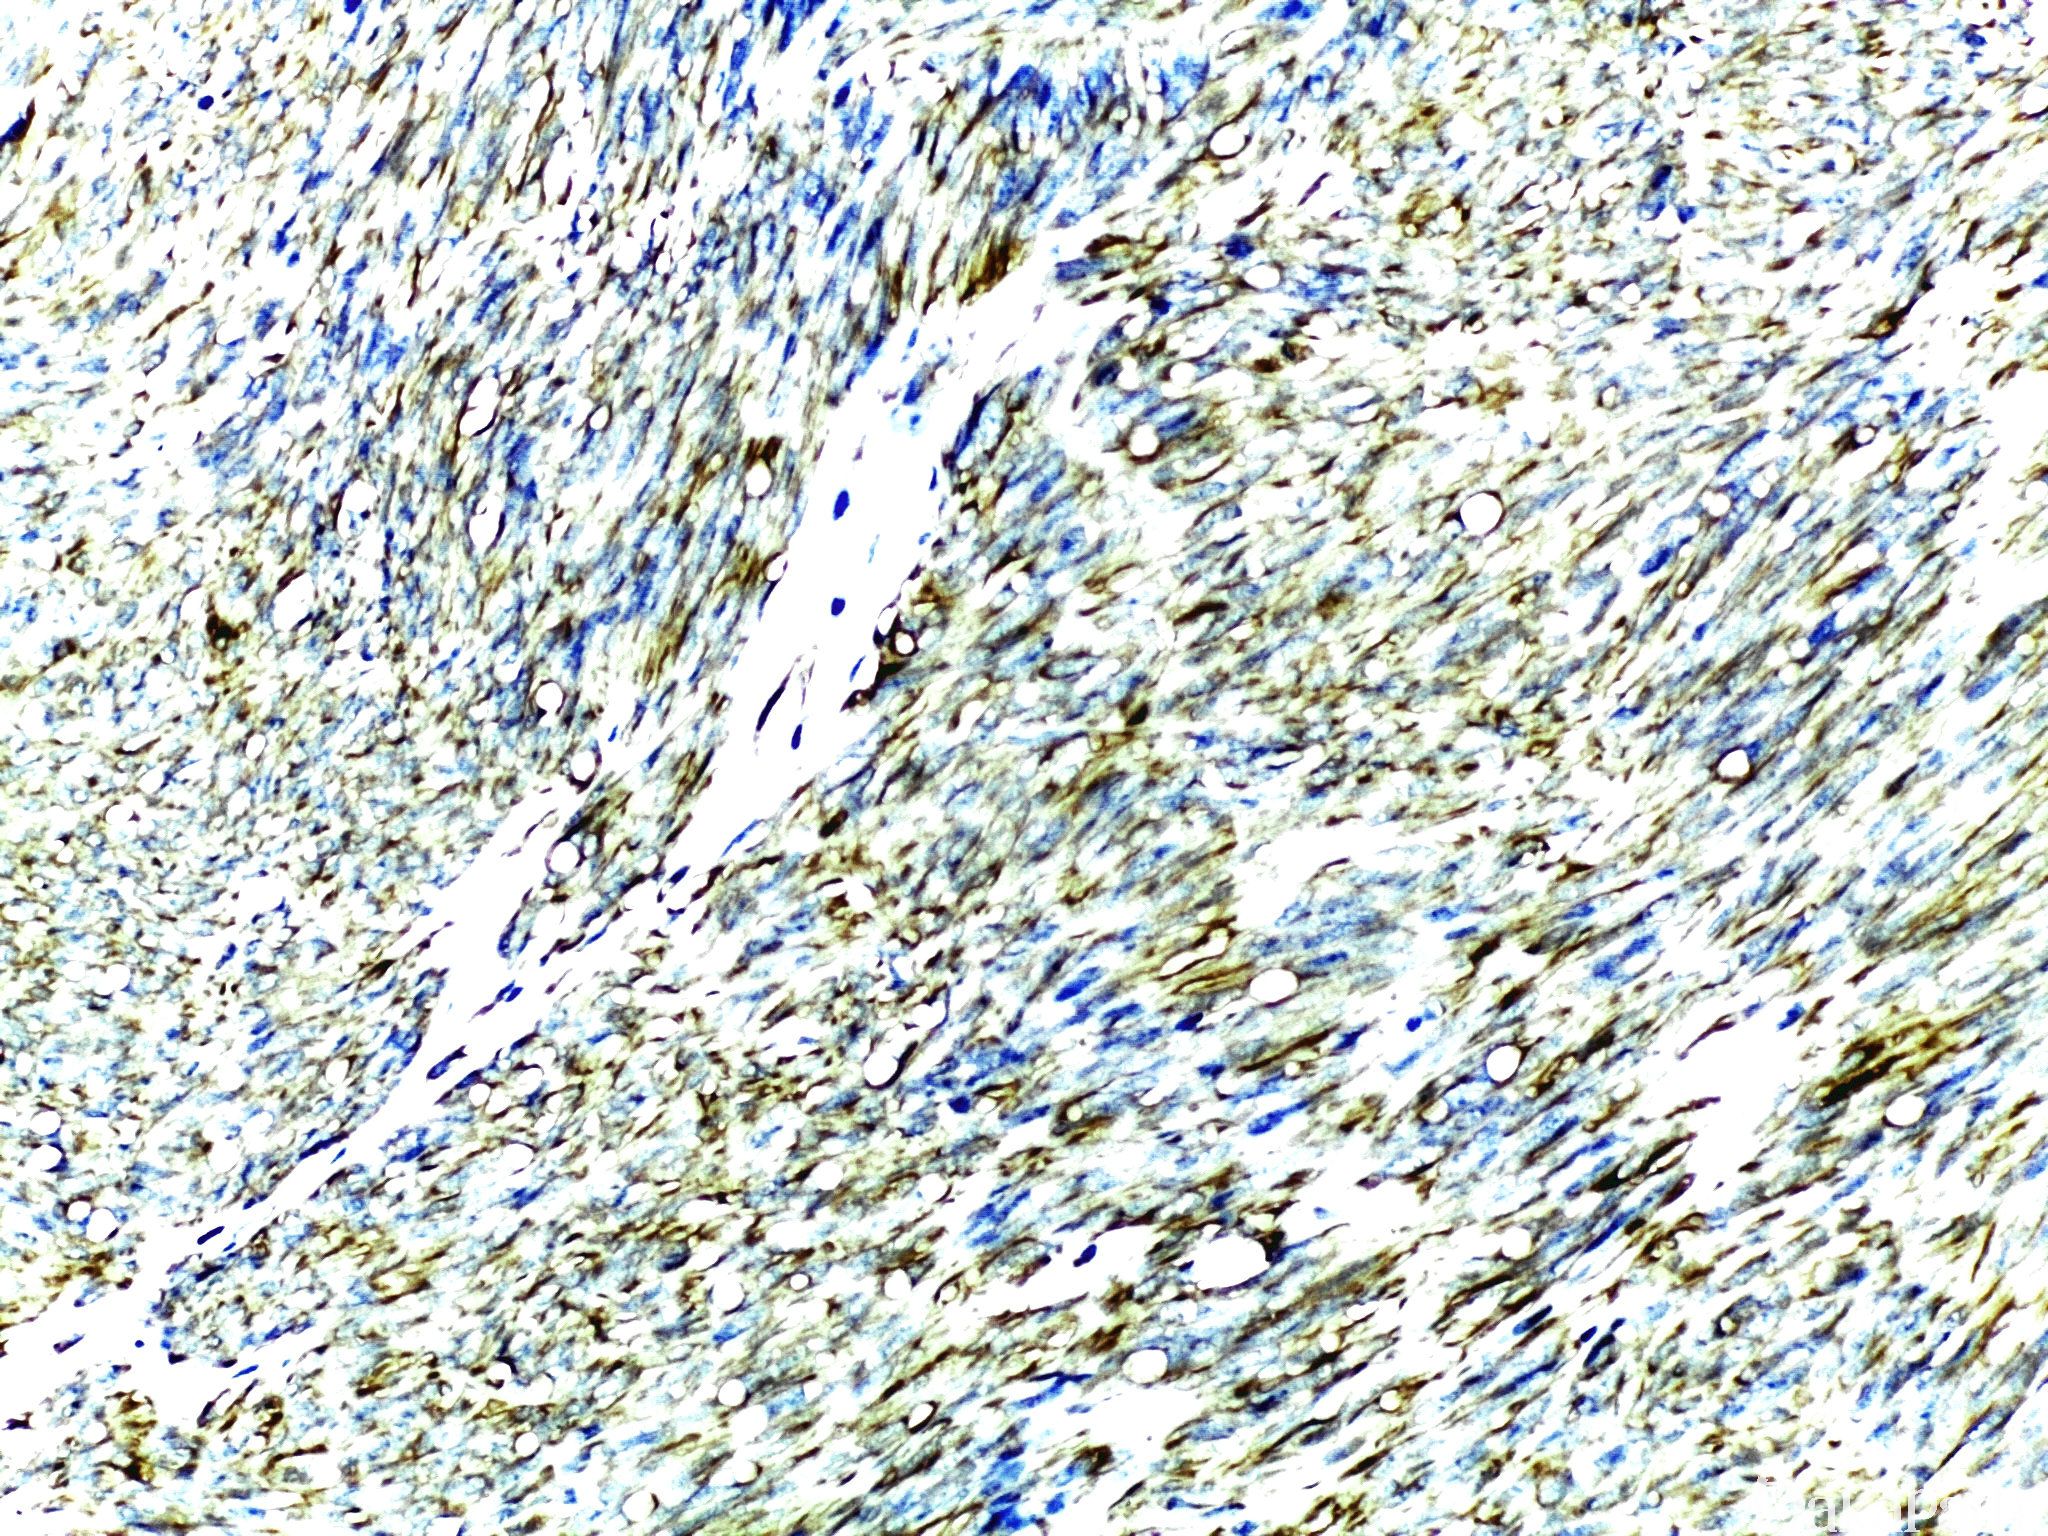

Nestin

中间丝蛋白的一种,存在于胚胎发育过程中有多向分化潜能的神经上皮干细胞。

信号定位: 胞浆

1. 胃肠道间质瘤与平滑肌肿瘤的鉴别诊断;

2. 原始神经外胚叶来源肿瘤阳性,如 PNET、髓母细胞瘤、嗅母、恶性畸胎瘤等幼稚神经细胞成分均阳性。

在肿瘤中的表达情况:

几乎全部阳性(≥95%的病例阳性): 颗粒细胞瘤、腺样囊性癌、胃肠道间质瘤

通常阳性(<95%,≥75%的病例阳性): 恶性黑色素瘤、神经鞘膜瘤,NOS、恶性外周神经鞘膜瘤、毛细血管瘤、血管肉瘤

经常阳性(<75%,≥55%的病例阳性): 汗腺透明细胞腺癌

有时阳性(<55%,≥35%的病例阳性): 微囊性附属器癌、痣,NOS、恶性潜能未定的平滑肌肿瘤、皮肤小汗腺腺癌、小汗腺汗孔癌、胰腺导管腺癌

少数阳性(<35%,≥15%的病例阳性): 孤立性纤维性肿瘤、滑膜肉瘤

偶尔阳性(<15%,≥5%的病例阳性): 尤文肉瘤

几乎全部阴性(<5%的病例阳性): 子宫内膜腺癌 I-II 级、腺泡状软组织肉瘤、皮肤黏液癌、乳腺外 Paget 病、乳腺 Paget 病、皮肤大汗腺腺癌